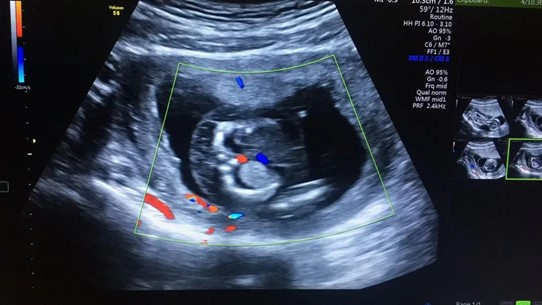

張女士本來是打算到武漢仁愛醫(yī)院做完產(chǎn)檢后,就和家人一起回老家過春節(jié),沒想到超聲檢查篩查出胎兒全身皮膚水腫,頸部淋巴水囊瘤,雙側(cè)胸腔積液,檢查醫(yī)生立刻叫來了武漢仁愛醫(yī)院超聲科主任王娟進(jìn)行再次檢查,確診了胎兒的異常情況。

張女士超聲檢查結(jié)果

“在這種情況下,胎兒需要進(jìn)行染色體的進(jìn)一步檢查,如果染色體有問題,就要盡早終止妊娠?!蓖蹙杲榻B,造成這一現(xiàn)象最常見的原因是孩子的染色體異常,在得了淋巴水囊瘤的孩子中,有70%是存在染色體異常的,這個(gè)和年齡相關(guān),年齡越大發(fā)生的概率越高,而這些孩子在早期如果出現(xiàn)了水腫,90%以上都不能夠存活,所以建議盡早終止妊娠。